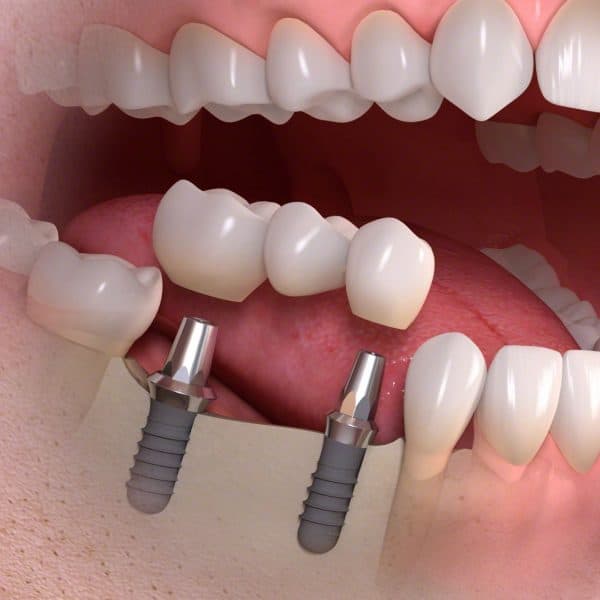

Oral Surgery & Implantology

Dental implant surgery can offer a welcome alternative to dentures or bridgework that doesn’t fit well and can offer an option when a lack of natural teeth roots don’t allow building denture or bridgework tooth replacements.